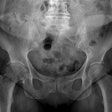

Imaging sheds light on complex cases of penile trauma